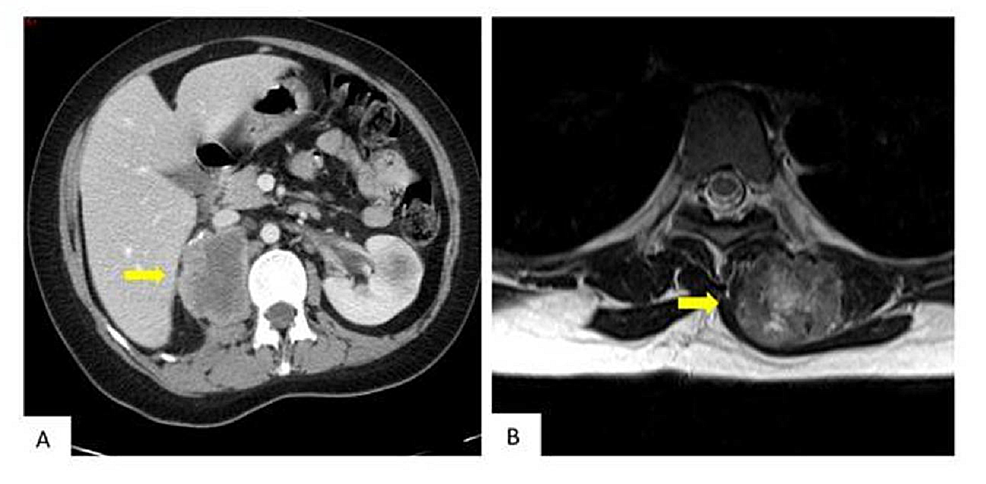

Abdominal and pelvic scans in January 2018 showed the progression of the tumor, disease in the right nephrectomy bed, and a new left renal lesion (Figure 5A). Magnetic resonance imaging (MRI) showed the persistence of the paraspinal lesion (Figure 5B). The clinically presented growth of the paraspinal mass was 15x11 cm. The patient declined further therapy and died of the disease in June 2018.